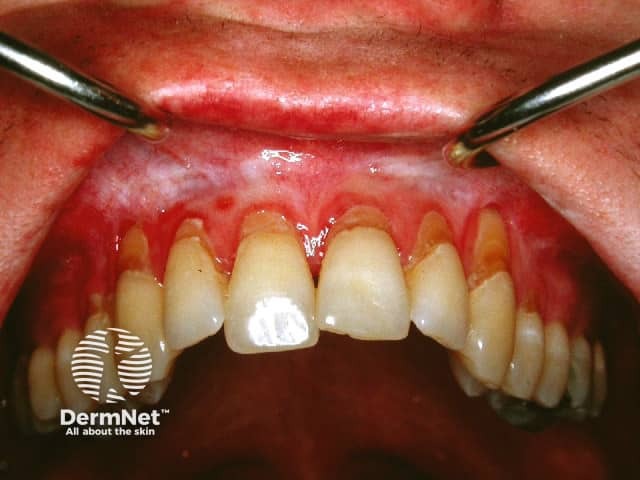

Atrophic/erosive lichen planus

Erosive pattern

Oral lichen planus can be very painful and ulceration may lead to scarring. Sometimes eating is so uncomfortable that the affected person is unable to maintain adequate nutrition.

Lichen planus, particularly the erosive form, may rarely lead to oral cancer (squamous cell carcinoma). Persistent ulcers and enlarging nodules should undergo biopsy.